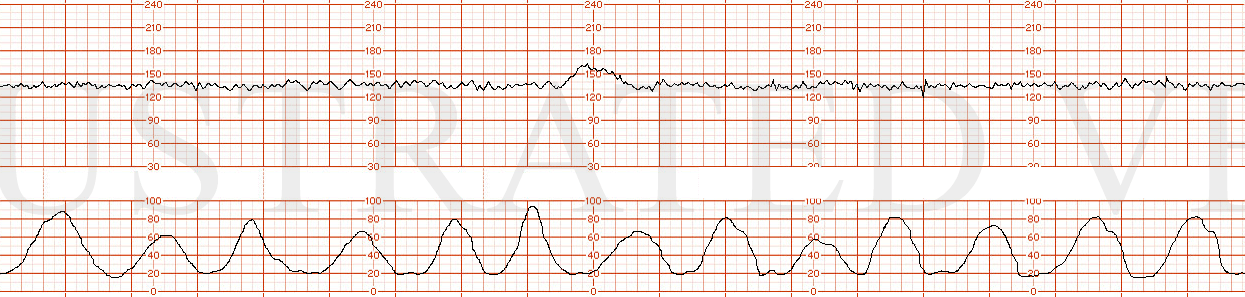

STRIP 71

1. 1st panel:

Contractions – average of 4 contractions / 10 minutes each symmetric x 60 seconds 3rd too long 30secs, 4th too long 20secs,

Baseline 1 – 145 with average variability

Decelerations 1 - none

Accelerations1 – none

2nd panel:

Contractions – 6 contractions / 10 minutes x 70 seconds with asymmetry to right i.e. 40sec after peak. (5th too long, shorten little, 8th make little longer)

Baseline2 – 150 with 3-5 bpm variability

Decelerations 2 – sporadic mild late decelerations – 10-15 bpm nadir x 1min with every 4th contraction with random nadir showing no progression in depth. (1st decel move 20-30 sec to left, 2nd decel move over the 8th contraction and make it look more gradual)

Accelerations2 – none; scalp stimulation negative response at 12 minutes into this panel. Write on strip point of scalp stim with no parallel accel.

STRIP 72

1. 1st and 2nd panel:

Contractions: 7-8 60-70 second contractions in 20 min. (2nd too long by40 secs, 4th take off 10 secs, last 2 take off 20-30secs) See exception below re deceleration associated contractions – 3 run together concluding 30 sec or so before end of deceleration.

Baseline 140 bpm for first 5 minutes w 7-8 bpm variability

Decelerations deceleration x 5.5 minutes to initial nadir of 110 bpm x 45 seconds, followed by gradual return to 140 bpm. The deceleration parallels a triple contraction with total duration of 5 minutes – first contraction relative magnitude 1; second .75 and third .5 magnitude of first.

Variability1 average / moderate at 145 pm after deceleration

Accelerations no accelerations after deceleration

3rd panel:

Contractions2: 7-8 60-70 second contractions in 20 min. Contractions at more predictable intervals with no coupling or tripling of contractions (2nd, 4th 7th contraction too long

Baseline2 140 bpm for first 6 minutes

Decelerations2 One deceleration x 6 minutes to initial nadir of 115 bpm x 35 seconds, followed by gradual return to 150 bpm baseline

Variability2 average / moderate at 6-7 bpm at 145 bpm baseline rate after deceleration

Accelerations2 no accelerations after deceleration